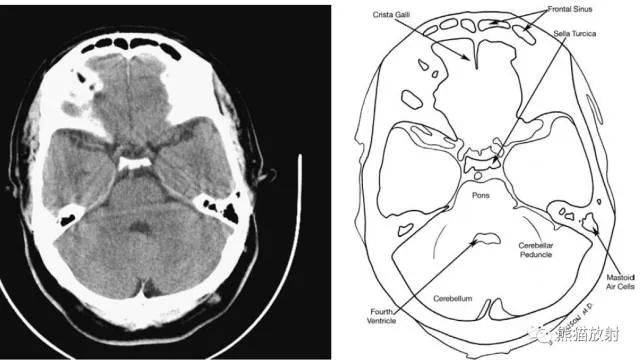

从前至后:上眼眶、颞下回、脊髓、小脑、乳突气房、乙状窦、四脑室、枕大池。

从前至后:额窦、鸡冠、蝶鞍、脑桥、小脑脚、小脑、四脑室。